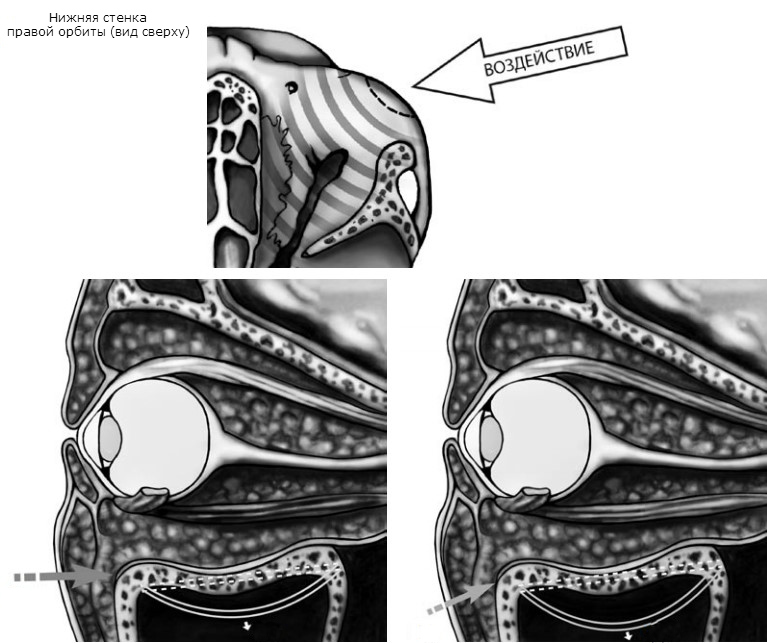

При обширных оскольчатых дефектах нижней стенки мягкие ткани не столько ущемляются, сколько смещаются вниз под воздействием силы тяжести и реактивного отека. Не столь многочисленные сторонники «механической» гипотезы, сформулированной R. Le Fort (1901), считают основным механизмом взрывного растрескивания дна орбиты волнообразные деформации, передающиеся с подглазничного края.

В зависимости от направления вектора силы дно орбиты (в первую очередь его внутренняя половина) испытывает или горизонтальную, или ротаторную деформацию. Площадь перелома будет максимальной в случае, если ранящий агент движется снизу-вверх под углом 30º к подглазничному краю. Кинетическая энергия, требующаяся для разрушения дна глазницы путем волнообразной деформации и через гидравлический удар, практически одинакова, но локализация и протяженность «гидравлических» и «механических» переломов существенно различаются. Экспериментальные исследования на кадаверных орбитах продемонстрировали, что переломы, обусловленные волнообразной деформацией, ограничиваются передней половиной внутренней части дна глазницы, не распространяются на медиальную стенку и не сопровождаются ущемлением мягких тканей в зоне костного дефекта.

Гидравлический механизм вызывает гораздо более протяженные переломы, захватывающие не только всю нижнюю, но и медиальную стенку глазницы, пролапс мягких тканей и энофтальм. По мнению некоторых авторов, в возникновении перелома играют роль оба механизма, и противопоставлять их в корне неверно. Одновременная инициация обоих механизмов травмы, их сосуществование, взаимодополнение с доминированием в каждом конкретном случае какогото одного варианта и объясняет многообразие орбитальных фрактур.